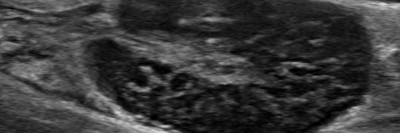

Warum schwillt die Wange beim Essen an?

Eine 42-jährige Patientin berichtet über seit zwei Wochen beim Essen auftretende Schwellungen an der linken Wange. Bei sauren Speisen seien diese besonders ausgeprägt. Seit zwei Tagen habe sie zunehmend auch Schmerzen, einen eitrigen Geschmack im Mund und die Schwellung bilde sich nicht mehr zurück.

Sialendoskopie/© UKL-HNO, Otoskopie bei einem jungen Kind/© SolStock / Getty Images / iStock (Symbolbild mit Fotomodellen), Speicheldrüsensonographie der Glandula parotis links bei Sjögren-Syndrom/© Zehrfeld N. et al. / all rights reserved Springer Medizin Verlag GmbH, Peritonsillarabszess links/© Matti Sievert et al. / all rights reserved Springer Medizin Verlag GmbH, Lymphknoten mit follikulärem Lymphom/© Meng S / all rights reserved Springer Medizin Verlag GmbH, Drehen einer Marihuanazigarette/© guruXOX / stock.adobe.com, IMRT-Bestrahlungsplan eines Ösophaguskarzinoms/© Rühle, A., Huber, P.E. / all rights reserved Springer Medizin Verlag GmbH, Masern, Mumps, Röteln im Impfpass/© Astrid Gast / stock.adobe.com, Aufziehen von Flüssigkeit mit Spritze/© Eisenhans / Fotolia, Skalpell/© imago, Histopathologisches Präparat/© K. Mantsopoulos et al. / all rights reserved Springer Medizin Verlag GmbH, Ultraschallbild der linken Glandula submandibularis/© V. Volgger, Doppelstenose des Ductus hepatocholedochus/© Springer Medizin, Search Icon, Infusion/© georgeoprea9 / Getty Images / iStock, Frau wird Blut abgenommen/© andresr / Getty Images / iStock (Symbolbild mit Fotomodellen), Junge Ärztin vor einem Triage-Zelt/© Milos / Stock.adobe.com (Symbolbild mit Fotomodell)